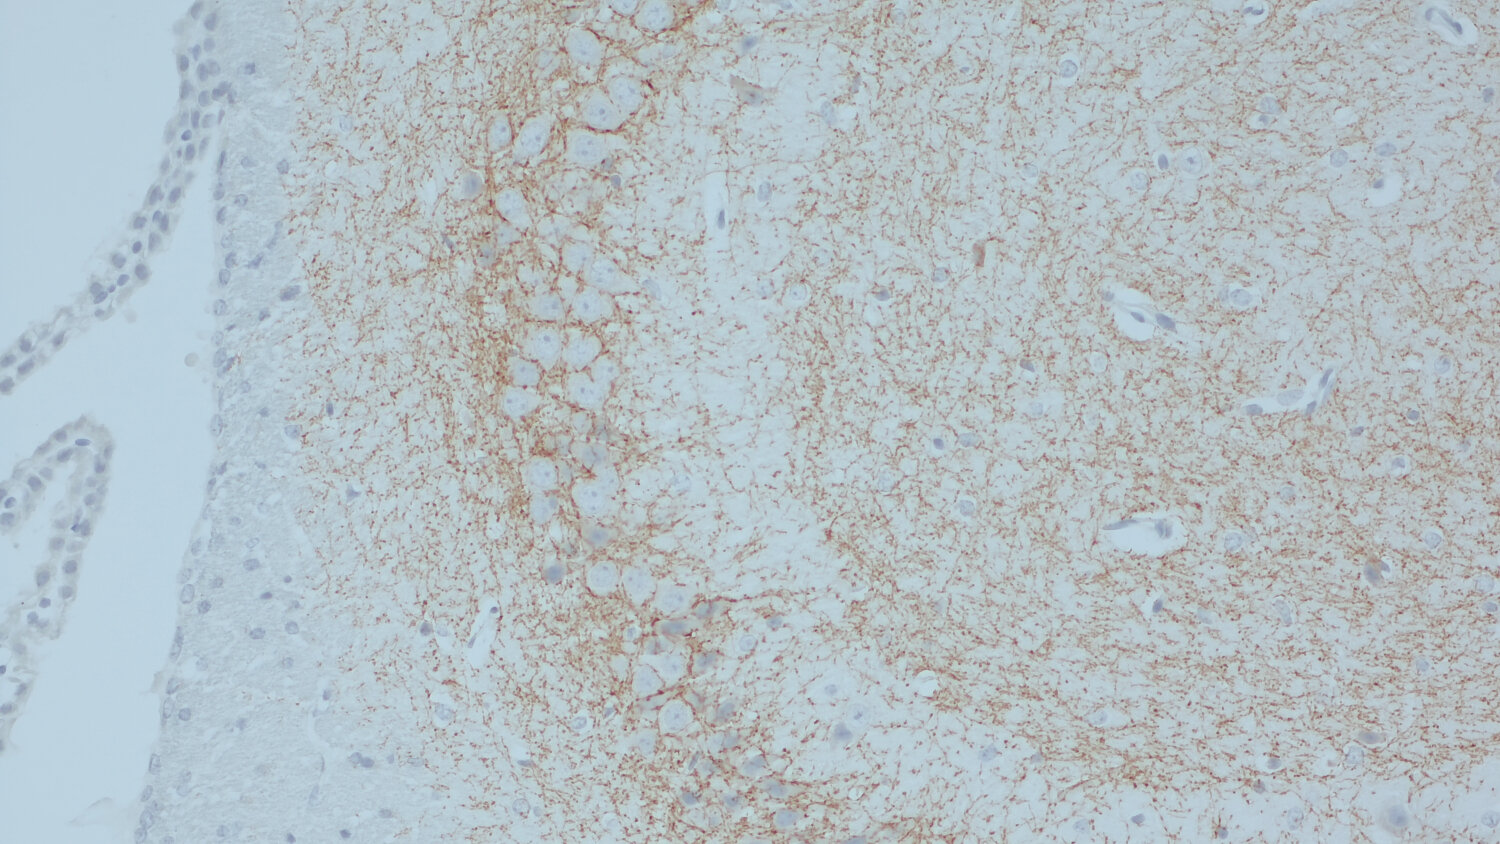

IHC: 1 : 500 gallery

IHC-P: 1 : 500 gallery

Immunohistochemistry (IHC) on 4% PFA perfusion fixed tissue with 24h PFA post fixation. Immunoreactivity is usually revealed by fluorescence or a chromogenic substrate. Some antibodies require special fixation methods or antigen retrieval steps. For details, please refer to the ”Remarks” section.